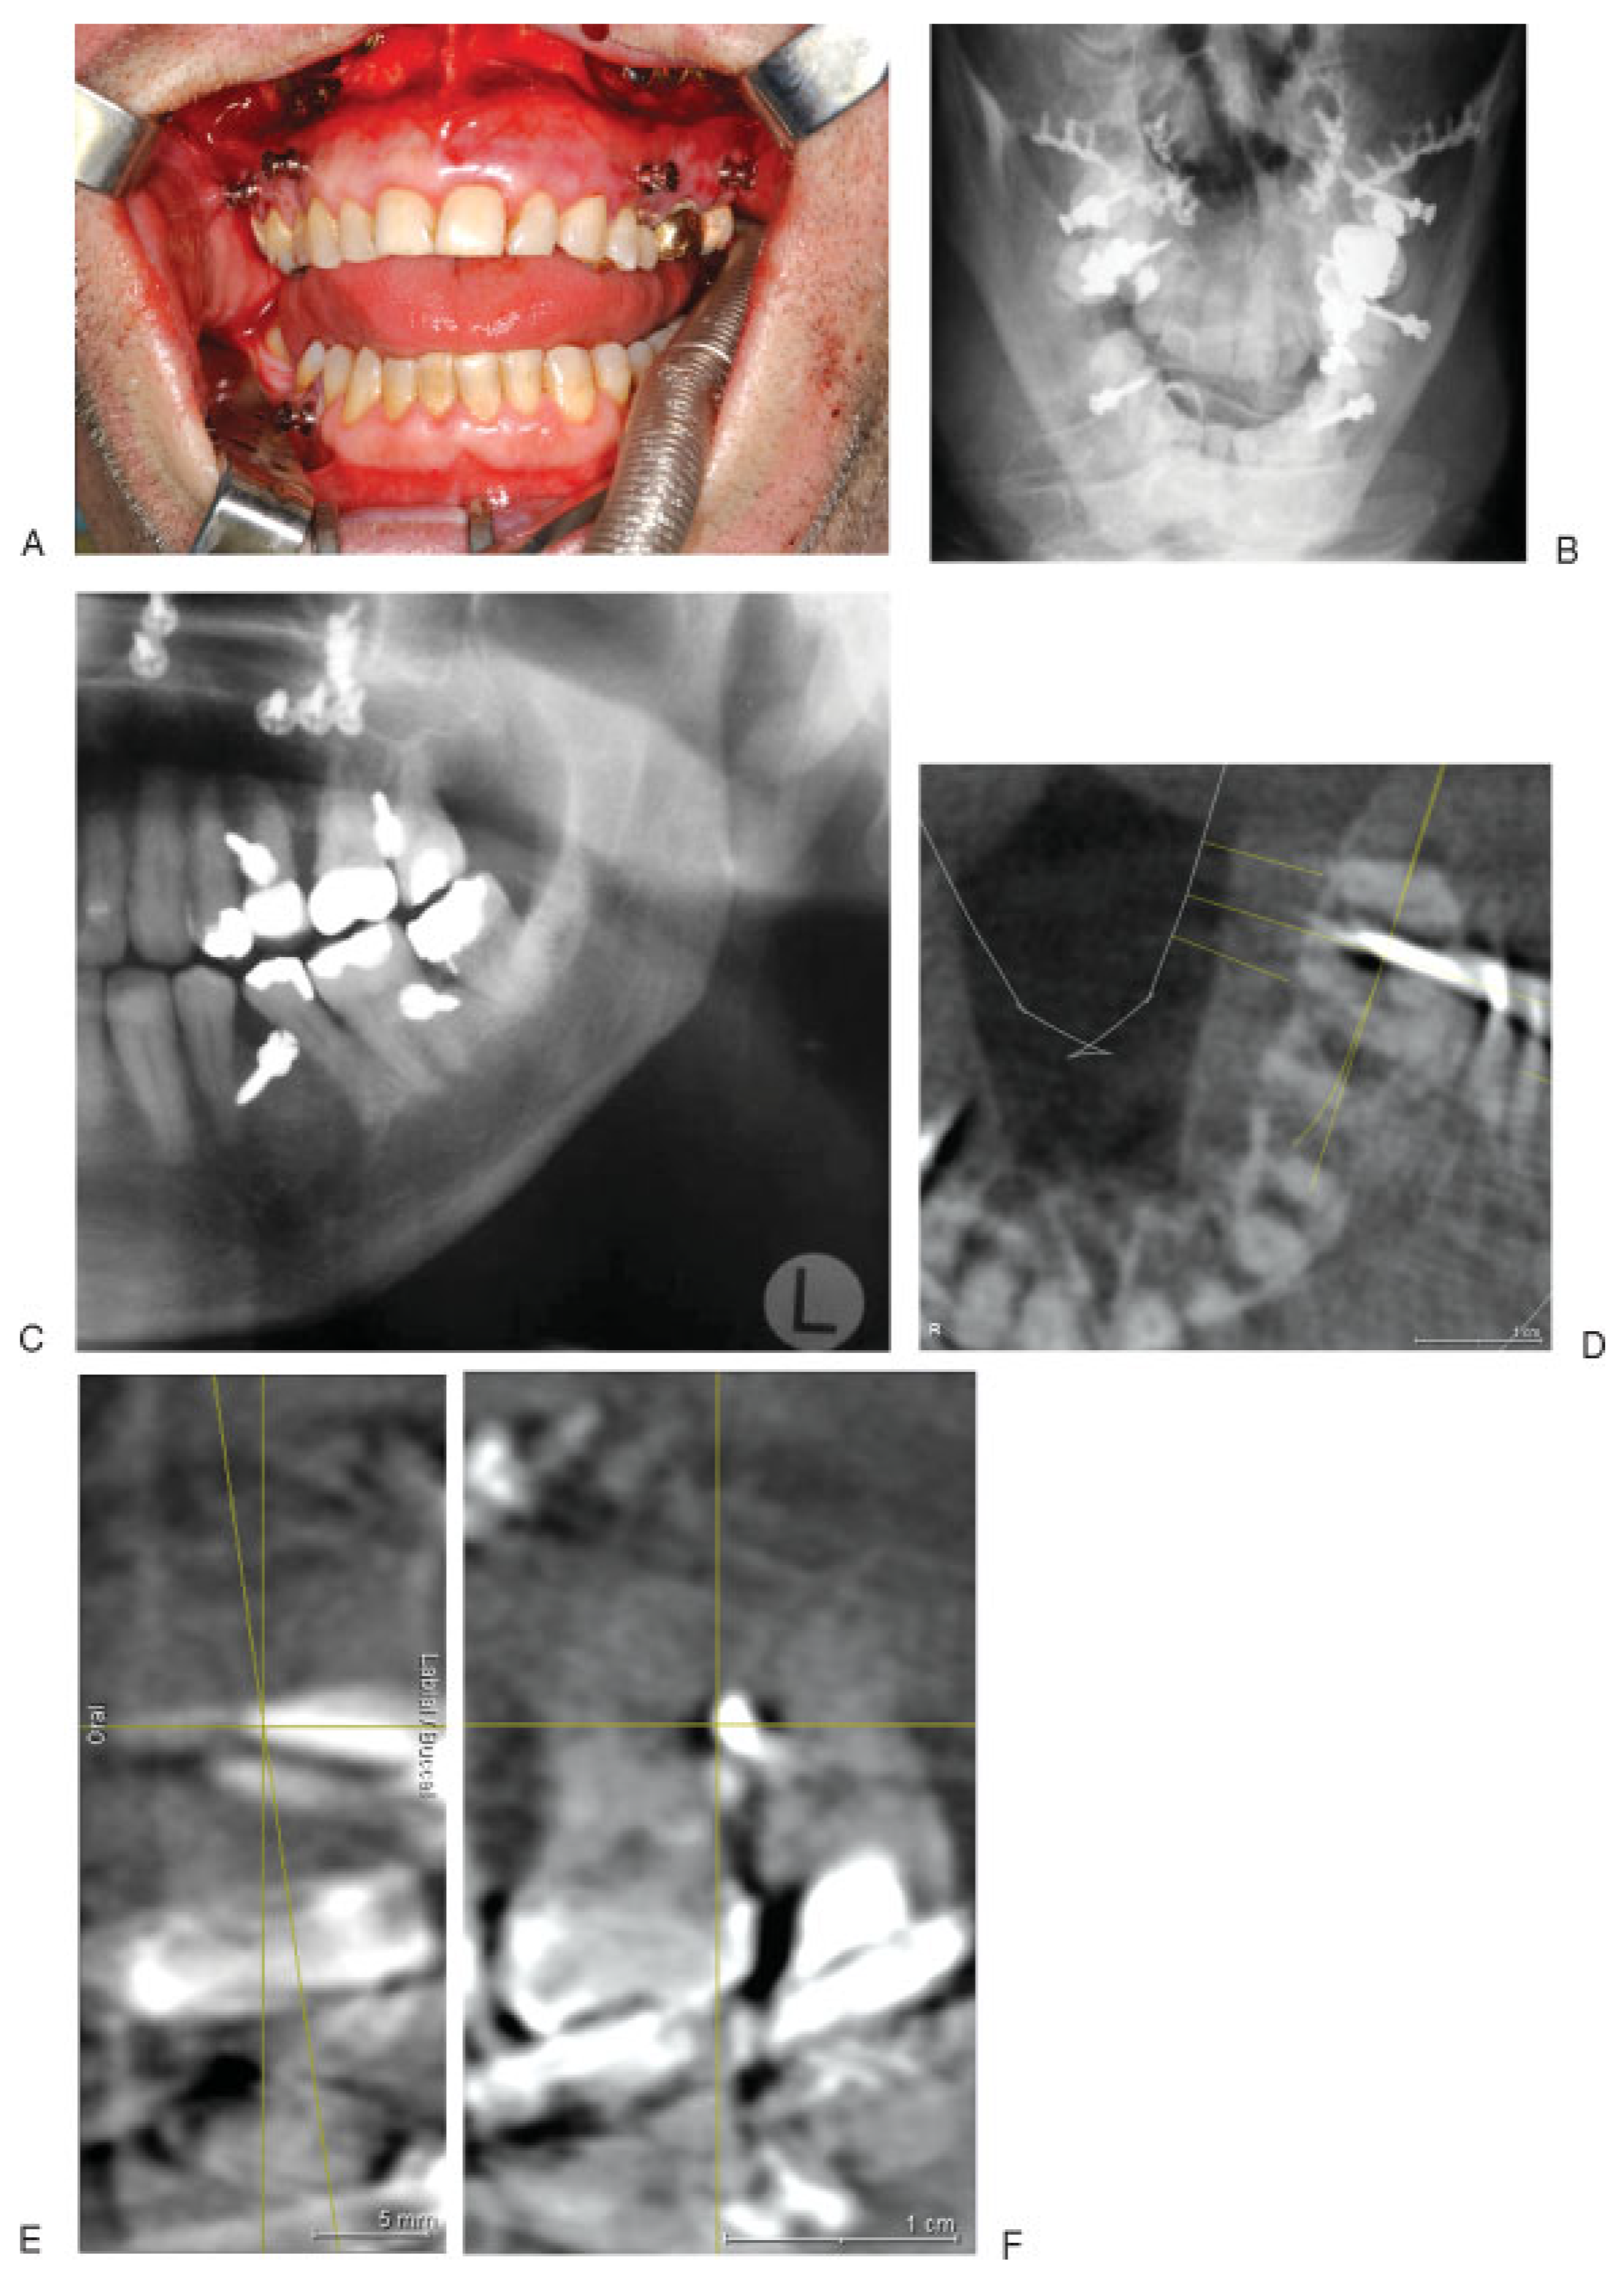

Figure 2. Lower half of the roots of permanent teeth exposed through a bone window in (A) left mandibular quadrant and (B) left maxillary quadrant. Note the width of the interdental bony septae diminishing toward the alveolar limbus and crest.

Figure 3. Colored CT scans highlighting the (A) mandibular and (B) maxillary tooth roots in axial planes. Note the tripoid configuration of the maxillary molar roots with the palatal roots at the medial outlet of the lingual roots.